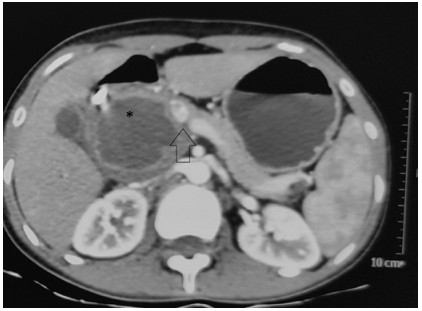

Abstract: Splenic vein (SV) ligation may be needed during portomesenteric junction resection, in pancreatoduodenectomy. Sinistral portal hypertension is a concern if the SV is not drained. Various techniques are described to reconstruct SV to avoid the variceal formation and sinistral portal hypertension which may lead to GI bleed. We describe a case of a 19-year-old female who underwent pancreatoduodenectomy for solid pseudopapillary neoplasm with portal-superior mesenteric vein junction resection and splenic venous was anastomosed into the interposition graft. We here share our unique experience of using an interposition internal jugular vein graft for a long venous defect and diverging morbidity of sinistral portal hypertension.